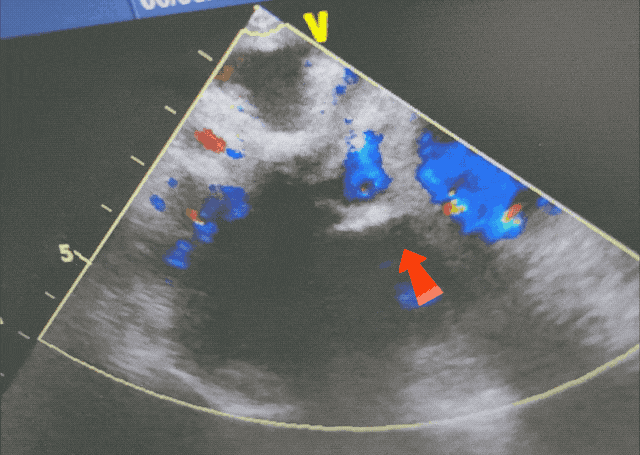

彩色血流显示封堵成功,无残余分流

PWD、CDFI:上述房间隔中断处可见左向右分流信号。二尖瓣口血流:E/A>1;三尖瓣口收缩期见反流信号+~++,峰速2.82m/s,压差31mmHg,估测肺动脉压41mmHg。